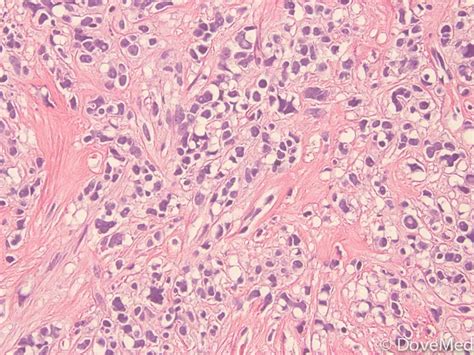

Hey everyone! Today, we’re diving into a topic that might sound a bit scary, but knowledge is power, right? We’re talking about metaplastic breast carcinoma . Guys, this is a rare type of breast cancer, making up less than 1% of all breast cancer diagnoses. But don’t let its rarity fool you; it’s important to understand what it is, how it differs from more common breast cancers, and what the outlook might be. Metaplastic breast cancer is unique because the cancer cells don’t just look like typical breast cancer cells under a microscope. Instead, they have a mix of cancerous cells, including those that have changed into other cell types, like squamous cells (think skin cells!) or cells that form cartilage or bone. This is what the term “metaplastic” refers to – a change in cell type. Because of this unique cellular makeup, metaplastic breast cancers can sometimes behave differently and may not respond to treatments that work well for other types of breast cancer, like hormone therapy. So, understanding these differences is super crucial for effective diagnosis and treatment planning. We’ll break down what makes this cancer stand out, discuss common signs and symptoms, explore diagnostic methods, and touch upon the treatment approaches. Stick around as we unpack this complex topic in a way that’s easy to understand.

So, let’s get into the nitty-gritty of metaplastic breast carcinoma . What exactly makes it so different from, say, invasive ductal carcinoma, which is the most common type? Well, the key lies in the cells, guys. In regular breast cancer, the cells usually originate from the milk ducts or lobules (where milk is produced). But in metaplastic cancer, the cells undergo a transformation, or metaplasia, becoming more diverse. Imagine a group of cells deciding to change their uniform – that’s kind of what’s happening! This can include cells that look like squamous cells (a type of epithelial cell) or even cells that can form mesenchymal tissue, like cartilage or bone. This mix of cell types means that metaplastic breast cancer often presents as a fast-growing mass, and it’s frequently larger at the time of diagnosis compared to other breast cancers. Another significant difference is how these cancers typically test for certain biomarkers. Most breast cancers are tested for estrogen receptors (ER), progesterone receptors (PR), and HER2. Many metaplastic breast cancers are negative for ER and PR, which means hormone therapies won’t be effective. They can also be HER2-negative. This lack of typical receptor expression is a major factor influencing treatment decisions. Because they don’t have these common targets, treatment often relies more heavily on chemotherapy and surgery. It’s also important to note that metaplastic breast cancer is often diagnosed at a later stage, partly due to its rapid growth and the fact that it might not show up on mammograms as clearly as other types. Sometimes, it can even be mistaken for a benign condition like a cyst or a fibroadenoma on initial imaging, delaying the diagnosis. This underscores the importance of thorough evaluation and biopsy when any suspicious lump is found. The rarity of this condition also means that research is ongoing to better understand its specific behaviors and to develop targeted therapies. For medical professionals, recognizing the unique characteristics of metaplastic breast cancer is vital for providing the best possible care.

Figuring out if you have metaplastic breast carcinoma involves a few steps, and it’s all about getting a clear picture of what’s going on inside the breast. The journey usually starts with a clinical breast exam , where your doctor will feel your breasts and lymph nodes for any abnormalities. If something suspicious is found, the next step is typically imaging tests . Mammograms are standard for breast cancer screening, but as we mentioned, metaplastic cancers can sometimes be tricky to spot on a mammogram. They might appear as a dense mass without the spiculated edges often seen in other cancers, or they might not be visible at all. Because of this, other imaging like a breast ultrasound is often used. Ultrasound is great for differentiating between solid masses and fluid-filled cysts and can provide more detail about a lump’s characteristics. Sometimes, an MRI of the breast might be recommended, especially if other imaging is inconclusive or to get a better view of the extent of the cancer. However, the definitive diagnosis of metaplastic breast cancer, like any cancer, comes from a biopsy . This is where a small sample of the suspicious tissue is removed and examined under a microscope by a pathologist. They look for the characteristic mixed cell types that define metaplastic carcinoma. During the biopsy, the pathologist will also perform tests to check for those important biomarkers: estrogen receptors (ER), progesterone receptors (PR), and HER2. As we discussed, these are often negative in metaplastic breast cancer, which significantly impacts treatment options. Pathologists might use special stains to identify the different cell types present. Sometimes, the initial biopsy might suggest a metaplastic carcinoma, but further testing or even a review of the surgical specimen after removal might be needed for a precise classification. The accuracy of the diagnosis is paramount, as it guides every aspect of the treatment plan. So, it’s a multi-pronged approach, combining physical exams, advanced imaging, and critical microscopic analysis to get to the bottom of it.